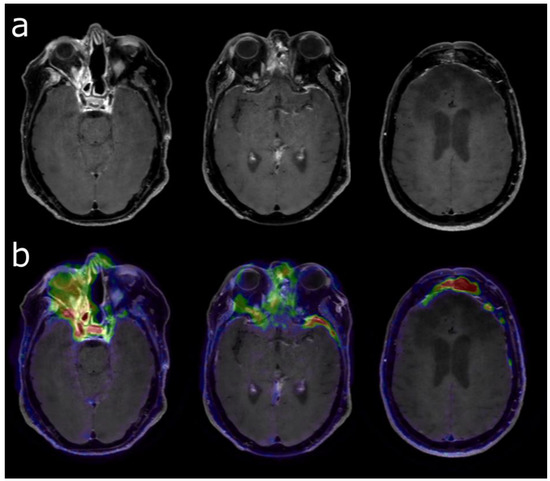

PET Imaging in Clinical Oncology | SpringerLink。Technology Focus – Diagnostic PET/CT Scan at Summit Cancer。What Does PET Imaging Bring to Neuro-Oncology in 2022? A Review。PETによるがん診断の専門書で、詳細な技術情報を提供。BLS 一次救命処置 AHAガイドライン2020準拠 プロバイダーマニュアル。。PET Scans Can Spare Lymphoma Patients Intensive Chemo。- タイトル: PET in Clinical Oncology- 著者: Helmut J. Wieler, R. Edward Coleman- ISBN: 978-3-7985-1219-1- 出版社: Springer- 言語: 英語- 内容: PETによるがんの診断と治療に関する詳細な情報を提供する専門書。ご覧いただきありがとうございます。医学生・研修医のための神経内科学